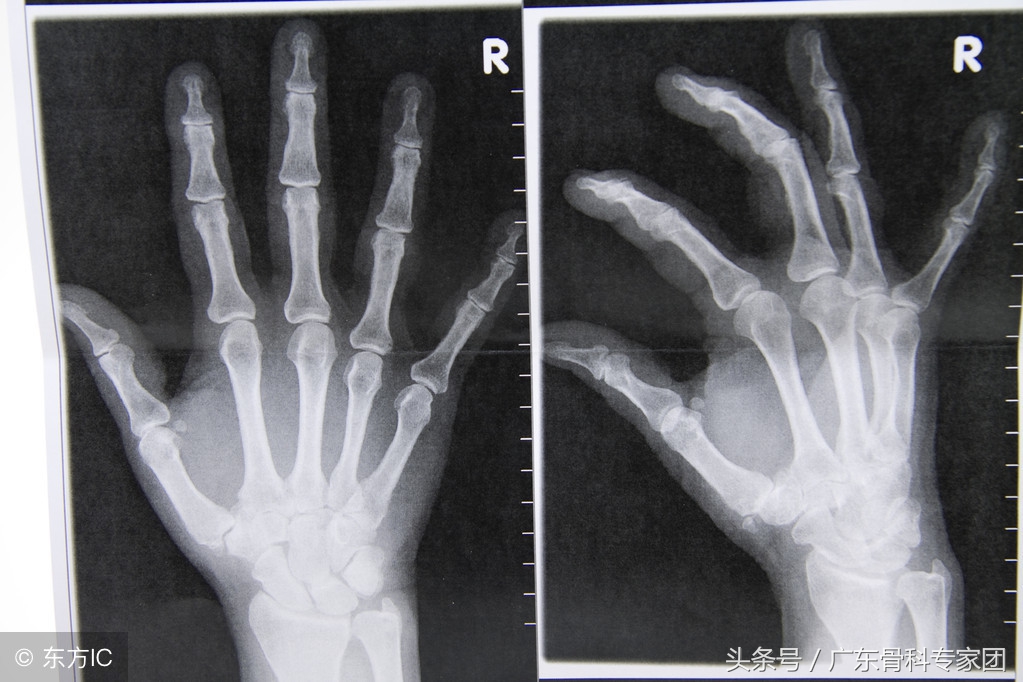

手腕骨折患者可能是因为意外导致摔倒的时候手掌撑地所致。手腕骨折患者的骨折类型大多数闭合性骨折。闭合性骨折是指局部的皮肤没有破损,常表现为局部的变形以及软组织的肿胀。手腕骨折分型有多种,因为受伤的机制以及骨折线的形态不同。最常见的分型是桡骨远端骨折。

2、绝大多数手腕骨折是可以通过手法整复来达到较好的复位效果的。在复位后需要进行固定,一般是采用石膏。通过固定来限制患肢的活动,从而避免骨折移位。